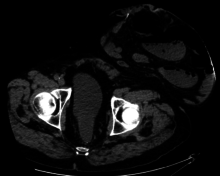

A colostomy is a surgical procedure in which an opening (stoma) is formed by drawing the healthy end of the large intestine or colon through an incision in the anterior abdominal wall and suturing it into place. This opening, in conjunction with the attached stoma appliance, provides an alternative channel for feces to leave the body. It may be reversible or irreversible depending on the circumstances.

Placement of the stoma on the abdomen can occur at any location along the colon, but the most common placement is on the lower left side near the sigmoid where a majority of colon cancers occur. Other locations include the ascending, transverse, and descending sections of the colon.[1]